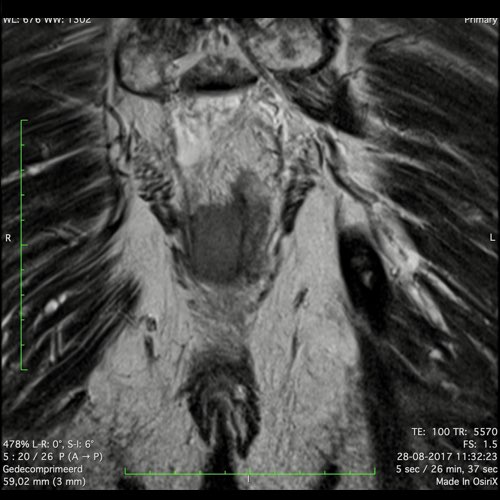

Hình ảnh

Các hình ảnh được cung cấp cho thấy ung thư biểu mô tế bào nhẫn với tình trạng dày lan tỏa thành trực tràng, hình ảnh bia bắn điển hình, và sự xâm lấn mỡ mạc treo trực tràng.